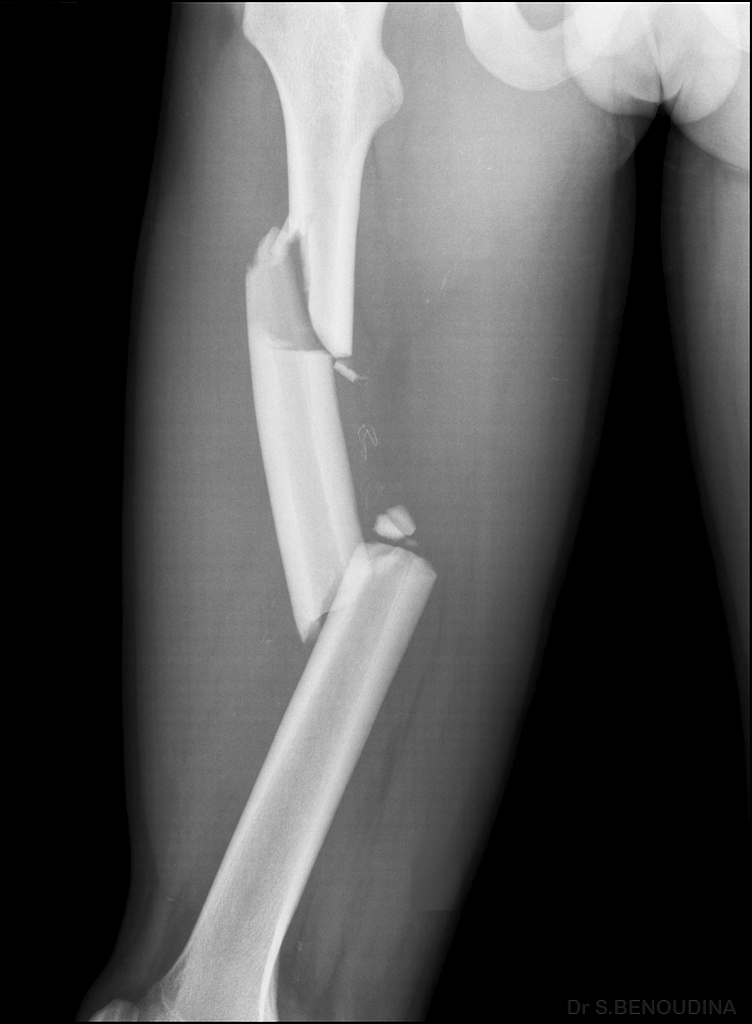

Forearm X Ray after Car Accident in Orthopedic Unit Inside Trauma Bone Fracture X Ray Description If no signs of trauma are seen, it is generally appropriate to negate skeletal damage and dislocations, with the latter word also excluding. When describing a fracture, displacement is important to assess and describe. A fracture of a short, flat or irregular bone requires a description determined by its direction through the bone. Displacement of fractures is defined in terms. Bone Fracture X Ray Description.